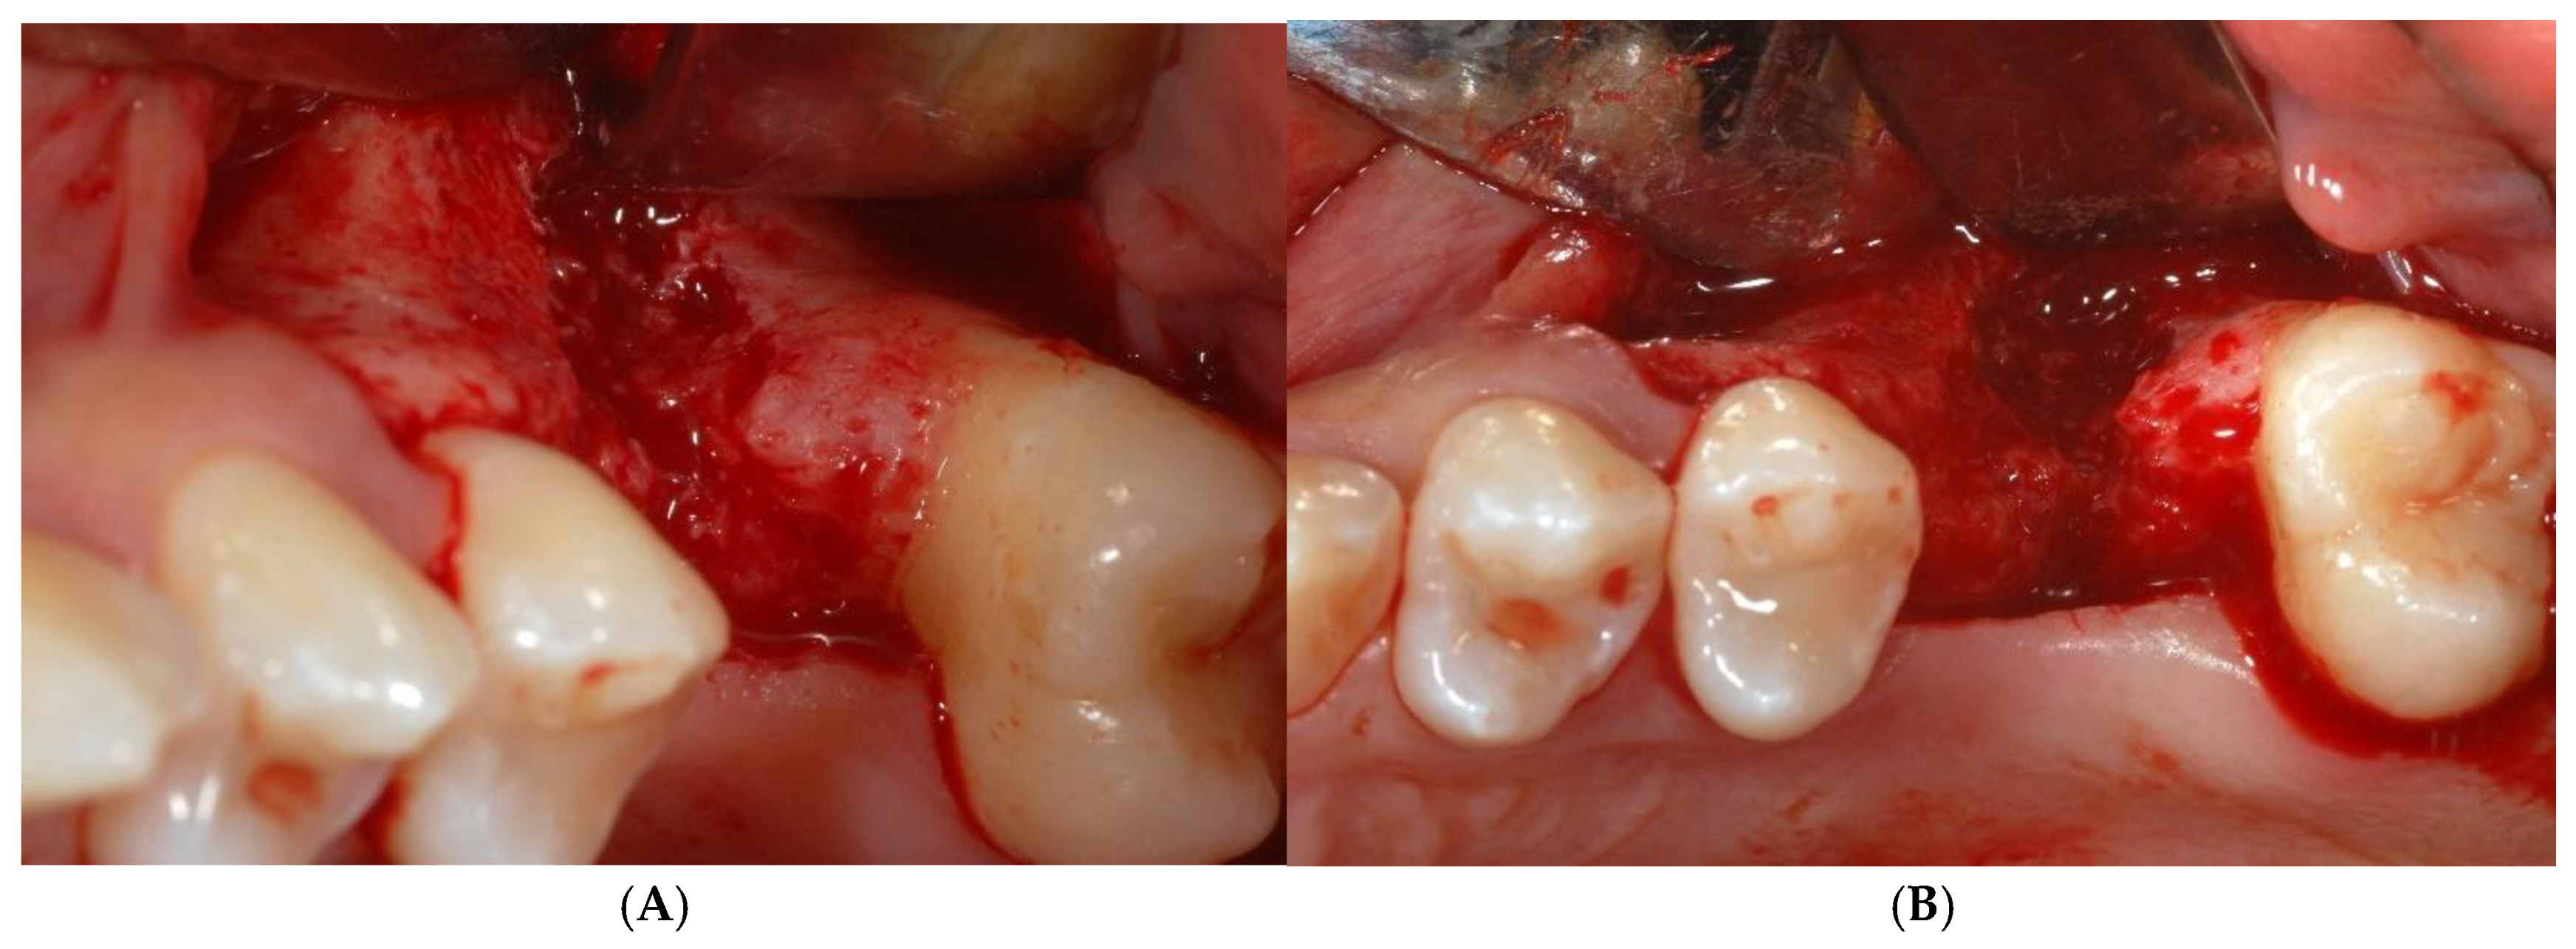

Figure 3.

After buccal flap reflection with two vertical releasing incisions, wide horizontal bone defect was evident (A,B).